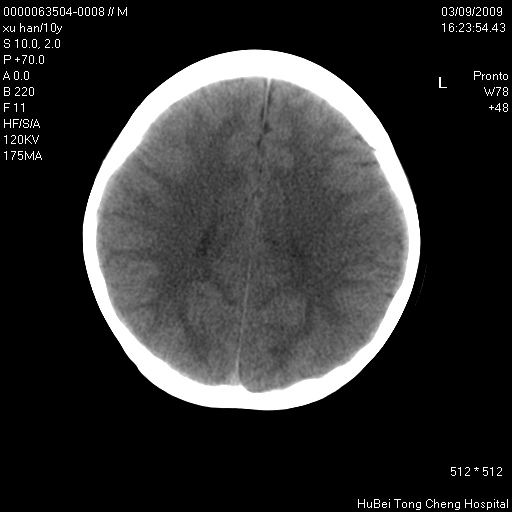

以下是引用道哥在2009-3-9 18:40:00的发言:[br]未见明显异常,必要时mr(dwi)成像。

以下是引用余辉在2009-3-10 11:01:00的发言:[br]考虑双侧海马急性缺氧性损伤